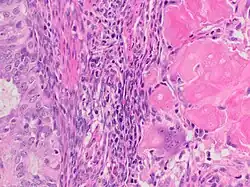

A ghost cell is an enlarged eosinophilic epithelial cell with eosinophilic cytoplasm but without a nucleus. It has lost its nucleus and cytoplasmic contents, leaving behind only the cell membrane and sometimes remnants of the cell's structure. In pathology, ghost cells are often associated with certain types of tumors, such as pilomatricomas and calcifying odontogenic cysts, where they appear as pale, anucleate cells that have undergone degeneration or calcification.

The ghost cells indicate coagulative necrosis where there is cell death but retainment of cellular architecture. In histologic sections ghost cells are those which appear as shadow cells. They are dead cells. For example, in peripheral blood smear preparations, the RBCs are lysed and appear as ghost cells.